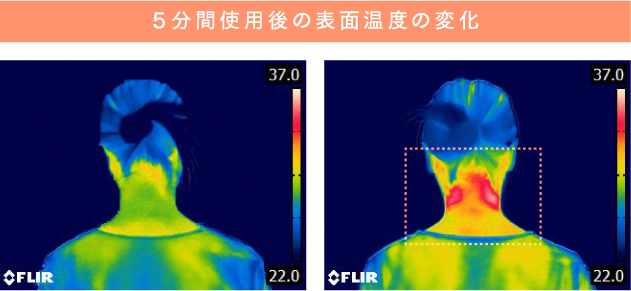

温熱で緊張をほぐす

首の深部まで温めてリフレッシュ

自重でより深くまで熱が伝わるので、首を温めながらリフレッシュできます。

首の緊張をほぐすことで、EMSと牽引機能による首ケアの質が高まります。

TOPICS

首を温めると良い入眠に繋がる!?

日本看護研究学会の論文によると、「40℃の温熱で15分程度、後傾部(首)温罨法を実施すると、眠気のある快をもたらす。」という研究データが発表されています。

研究結果によると、首を温めることで

心地よさや眠気が手に入る。

という事実!

※【参照論文】後頸部温罨法による自律神経活動と快-不快の変化。

日本看護研究学会雑誌/34 巻 (2011) 2号